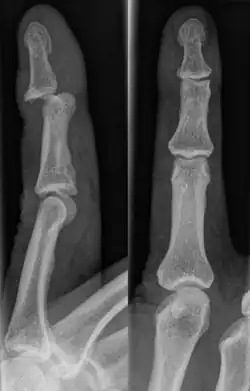

A jammed finger can generally be diagnosed by a physical examination. Bone or joint deformity may indicate potential dislocations or fractures.[6] The basic structure of the finger includes three bones with joints in between each.[9] The joint closest to the tip is the distal interphalangeal (DIP) joint. The next joint, moving closer to the hand, is the proximal interphalangeal (PIP) joint. The thumb differs by only having two bones and one interphalangeal joint.[10]

The injured finger may be examined to determine where the pain is worst.[3] If the finger is sprained or dislocated, pain will be worse at the joint rather than the bone.[3] Due to the risk of dislocations or fractures, X-rays should be conducted prior to testing joint stability. This allows for prior detection of a dislocation or fracture.[3] It is recommended that a variety of views (lateral, oblique, and anteroposterior) are observed.[3] In extremely painful cases, a digital nerve block may be done to better assess the finger. This is where anesthetic is injected to either side of the base of the affected finger to reduce pain.[3]

Fractures are instances where the bone's structural integrity has been compromised.[20] If a jammed finger produces a fracture, pain will be greatest at the bone as opposed to the joint.[2] There may also be visual deformation of the bone itself.[6] As with any skeletal injury, an x-ray can be conducted to verify the presence of a fracture.[1] The distal phalanx is especially vulnerable to avulsion fractures.[1] These avulsion fractures are common following a first time dislocation of the DIP.[1]